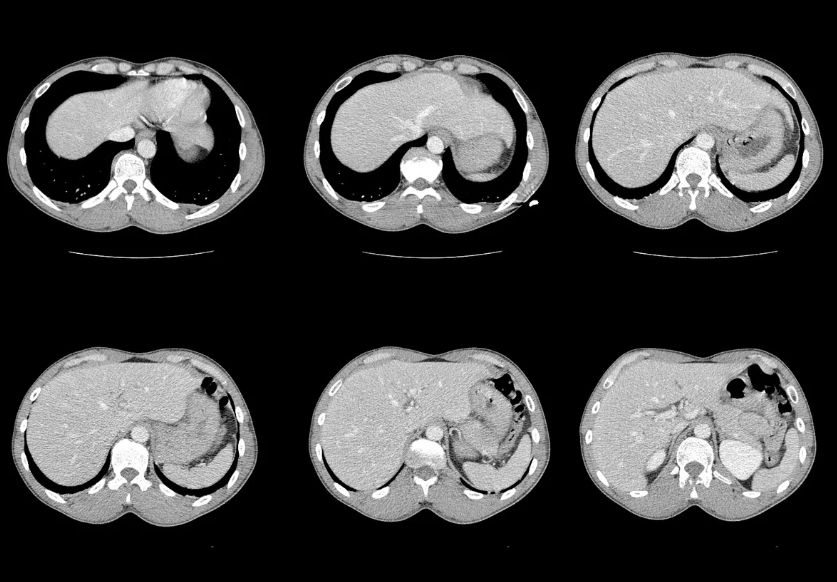

La tomografía computarizada (TAC) es un examen de imagen que utiliza rayos X y tecnología computarizada para obtener imágenes detalladas del cerebro, los huesos del cráneo y las estructuras internas de la cabeza.

A diferencia de una radiografía convencional, la tomografía permite obtener cortes transversales en tres dimensiones, lo que facilita la detección de alteraciones con alta precisión.

En términos simples, es como observar el cerebro y el cráneo por “capas”, lo que facilita identificar lesiones, sangrados, tumores o inflamaciones que podrían pasar desapercibidas con otros métodos diagnósticos.